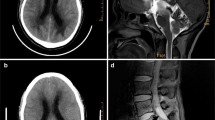

Morphological analysis of TTR CNS involvement (leptomeninges, vessels, and parenchyma) was based on anti-TTR immunostained sections. The presence and degree of amyloid deposition was analyzed semi-quantitatively by a neuropathologist (RT) blinded to patient´s clinical features. Amyloid vessel deposition was classified as negative if no TTR positive vessels were found; mild if scattered positivity was found in few vessels; moderate if scattered positivity in many vessels or strong positivity in few vessels was found; and severe if strong positivity in many vessels was found [4] (Fig. 1). In the leptomeninges and brain parenchyma, the amyloid deposition was classified as negative, if no amyloid deposition was found, and as mild, moderate, and severe according to the amount of immunoreactivity present [21] (Fig. 1).

Examples of CNS TTR stages. Stage 1 (1a-1c), stage 2 (2a-2c), and stage 3 (3a-3c). Leptomeninges and subarachnoid vessels are involved earlier, including in the brainstem region in stage 1. In stage 2, there is increased severity of the amyloid deposition and involvement of the perforating cortical vessels and subpial region. Finally, in stage 3, amyloid load continues to increase and there is additional amyloid deposition in the subependymal and basal ganglia vessels near the ependymal lining. Scale bar—200 µm